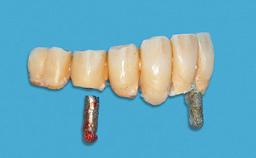

Attachment One-Piece

Abutment Type Standard

Prosthesis Type RDP

Defining Characteristics Fully edentulous lower jaw to be rehabilitated with an implant-borne removable overdenture